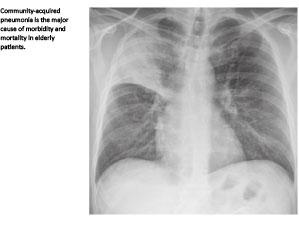

Introduction: Community-acquired pneumonia (CAP) is a major cause of morbidity and mortality in elderly patients, and the most important cause of death in the developed world. Optimised treatment and care will benefit patients as well as the health economy. This study investigates in-hospital compliance with guidelines for treatment and care of patients with CAP.